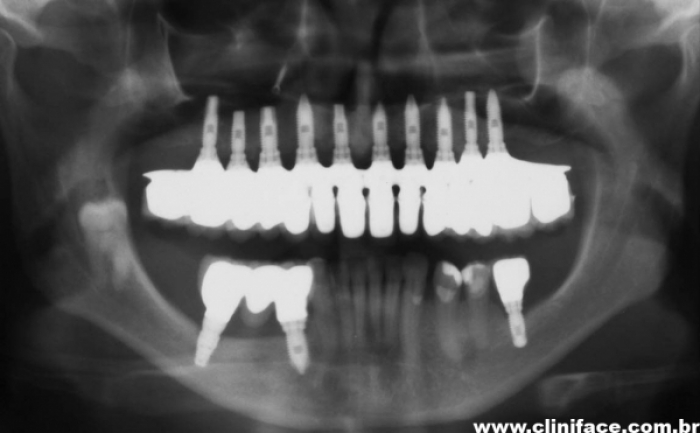

Raio X inicial